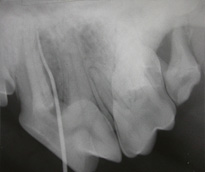

Endodonti